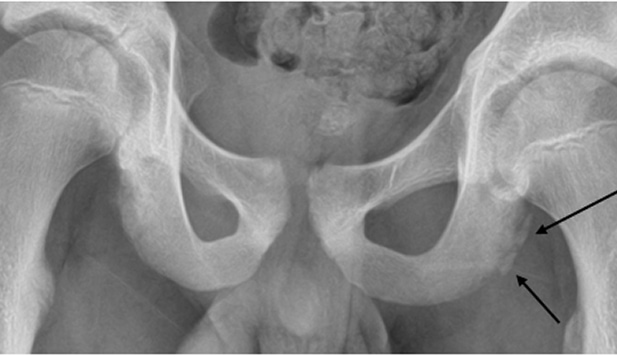

This patient has an avulsion fracture of the ischial tuberosity, seen as displacement of the apophysis.

- This injury is seen most commonly seen in young athletes, especially soccer players. It results from sudden, forceful contraction of the hamstrings

- Patients in puberty and late adolescence are at greatest risk, as this is a time when the secondary ossification centre or apophysis is weakest in the chain of muscle–tendon–bone

- Radiograph of the pelvis should be performed in adolescent patients with a history of proximal hamstring injury and current ischial tenderness

- Displaced avulsion fragments or chronic nonunion fragments may require surgical repair.